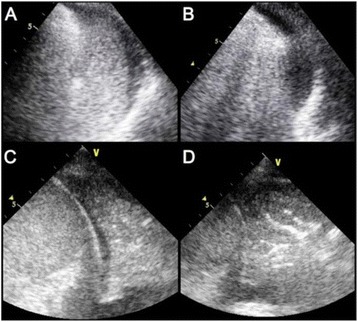

P094 - Lung ultrasound before and after fiberbronchoscopy - modifications may improve ventilator-associated pneumonia diagnosis

S. Mongodi, B. Bouhemad, A. Orlando, A. Stella, G. Via, G. Iotti, A. Braschi, F. Mojoli